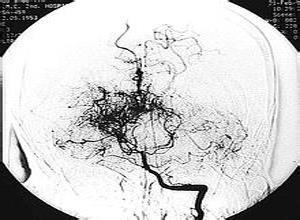

简介烟雾病又称为Moyamoya 病或自发性基底动脉环闭塞症,是一种以 Willis环双侧主要分支血管如即双侧颈内动脉末端及大脑前、大脑中动脉起始部动脉内膜缓慢增厚,动脉管腔逐渐狭窄以至闭塞,继发出现侧支异常的小血管网为特点的脑血管病。因脑血管造影时呈现许多密集成堆的小血管影,似吸烟时吐出的烟雾,故名烟雾病,Moyamoya是日语"烟雾"的发音。本病的实质是脑底部动脉主干闭塞伴代偿性血管增生。